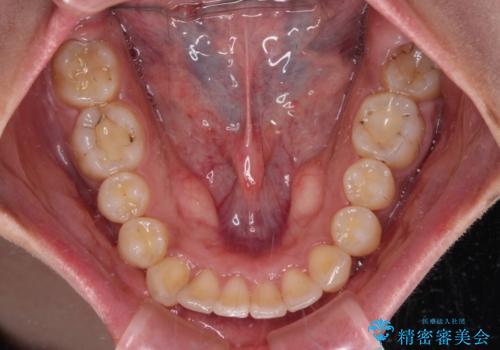

深い咬み合わせと前歯のデコボコ インビザラインによる矯正治療

治療途中では、左右ともに奥歯が咬みにくい状態が続き、問題なく噛めるようになるまでに長期間を要しました。

一方で、デコボコや下顎の前歯が隠れてしまうほどの深い咬み合わせはしっかりと改善されました。